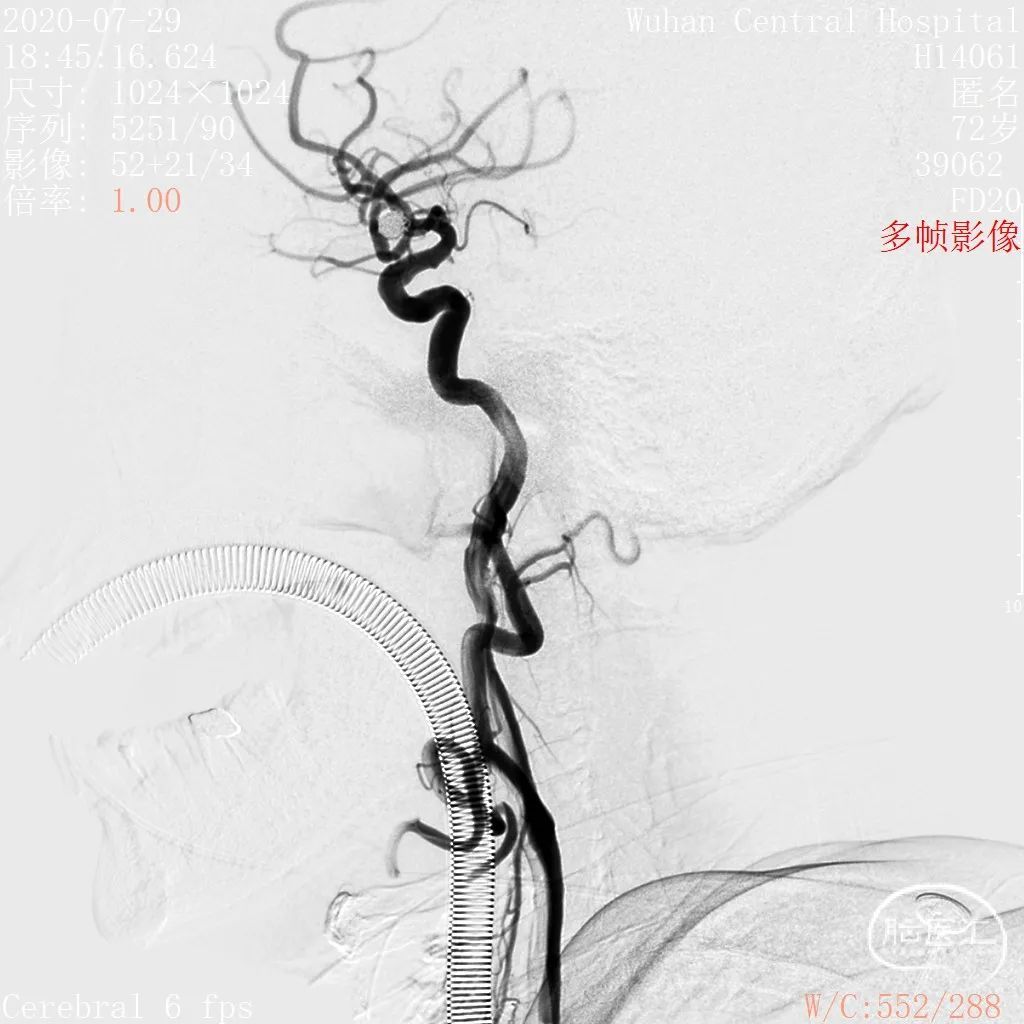

术前影像

DSA 2020-07-29

工作角度

术后影像

术后 DSA

术后颈总动脉通路通畅